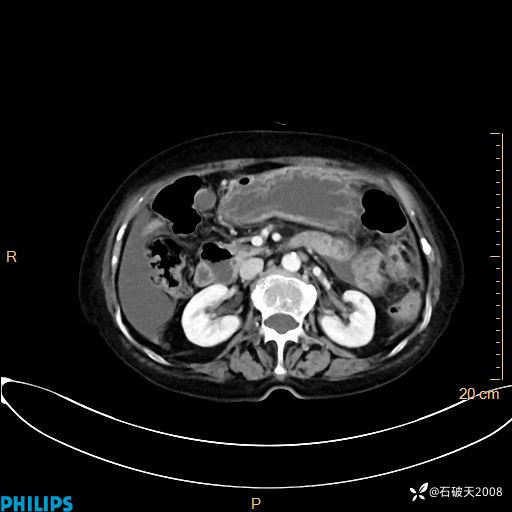

平扫